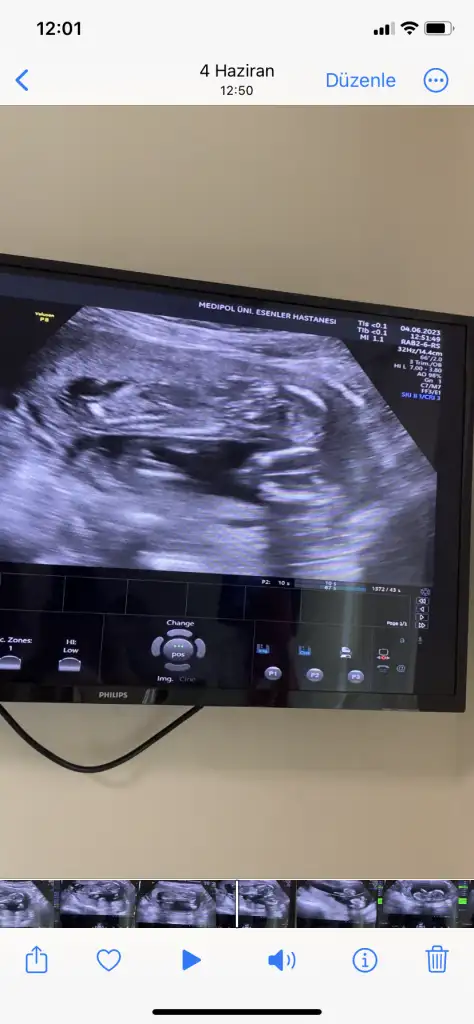

Bacak arası gibi ama çekimden mi bu kadar büyük bacakları, belki de değildir. Normalde böyle kalın ve kısa oluyorlarsoyasosu vu 14. Haftalıkken kendi doktorum 2. Bebegin poposunu görememişti ekrana sığmıyo diyerek bende videodan inceledim üstteki bebege bakarken alttaki bebegin bacak arası değilmi o benmi yanlış görüyorum

Vidodan baktım kesiin bacak arası canım ilk fotodakide bacak arası farklı bi açı orda çıkıntı var klitoris olsa 14. Haftada kaybolurdu heralde bilemedim iyiceBacak arası gibi ama çekimden mi bu kadar büyük bacakları, belki de değildir. Normalde böyle kalın ve kısa oluyorlarbaşka varsa atarsan bakarız birlikte

Burada hiç anlayamadımVidodan baktım kesiin bacak arası canım ilk fotodakide bacak arası farklı bi açı orda çıkıntı var klitoris olsa 14. Haftada kaybolurdu heralde bilemedim iyice

Devlet bişey vermedi görmedimde bugün kızda bacak arası daha boş ordan belli gibi kendi doktorum o gün kemik yapısına göre kıza benzettiğini söylemişti diğerini göremedim dedi ama videoda bi çıkıntı gördüm ben şimdi detaylı baktım cumartesi giderim netleşir inşallahBurada hiç anlayamadımama erkek olunca anlamak çok kolay oluyor. Videoda 3 çizgi belli mi kızda